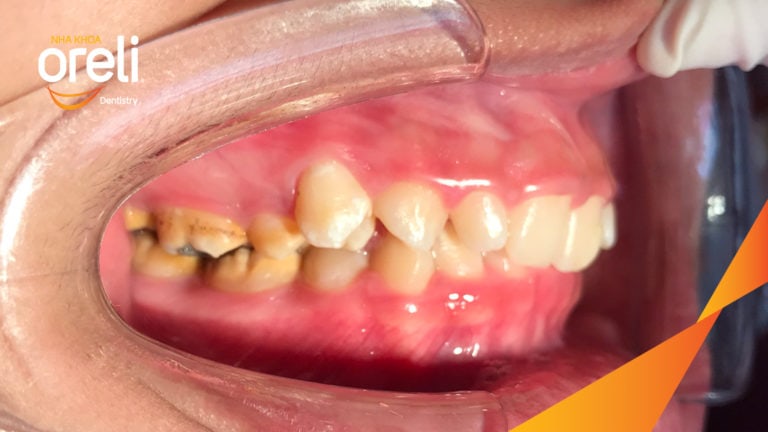

Ca niềng chỉnh cắn sâu nặng kèm cắn chéo vùng răng sau kết quả thực tế tại nha khoa Oreli Niềng răngCắn sâu Xem thêm